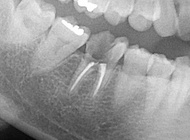

ブリッジは片方外れても分かりにくい?

三鷹市、ファミリー歯科医院、院長の佐野真弘です。 この患者さんですが、ブリッジが噛むと違和感がある、ということで来院されました。 レントゲン写真を撮ってみると何と片方の歯がブリッジから外れてしまっている状態でした。 &n…